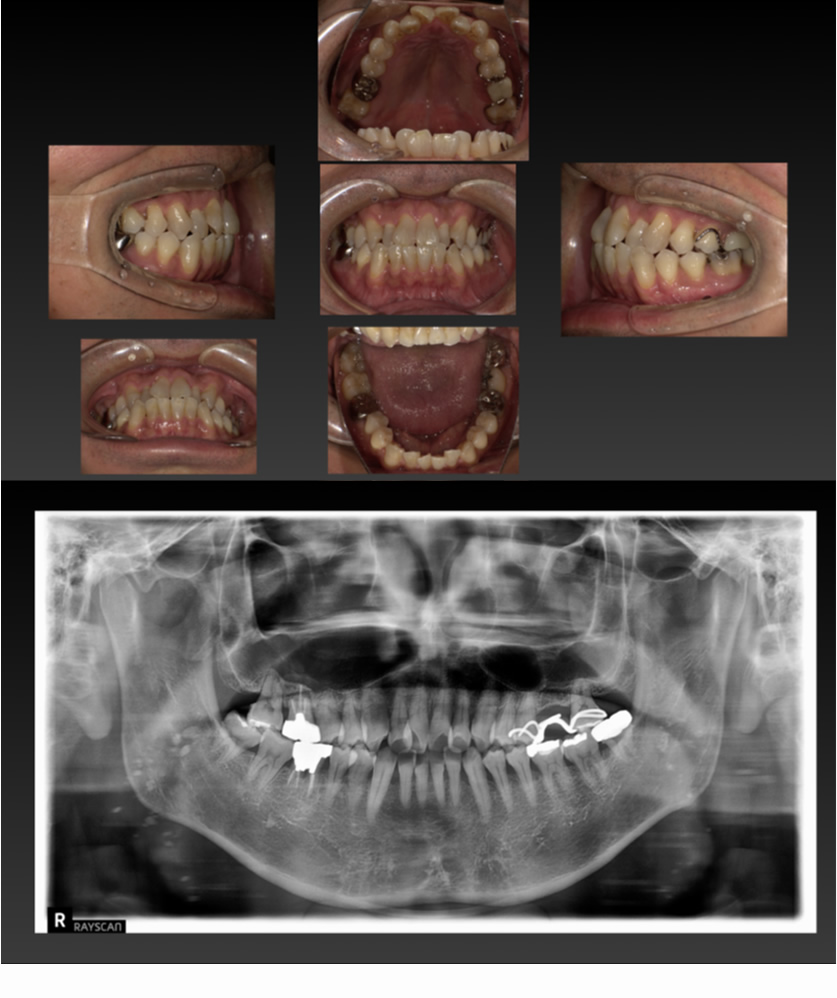

04 症例

04 右下の歯が割れ、左上が入れ歯なのでインプラント希望

Before

After

| 治療内容 | 右下の歯が割れている、左上が入れ歯なのでインプラント希望 |

|---|---|

| 患者さま | 50代男性 |

| 主訴 | 根が割れていて痛いのと、入れ歯の管理が大変なのでインプラントにしたい。 |

| 治療期間(目安) | 3ヶ月 |

| 治療費(税込:目安) | ¥984,500 |

| リスク | 術後に多少の痛みや腫れが出ることがある。歯肉退縮がおきると、歯と歯肉の間に隙間が生じることがあります。 |